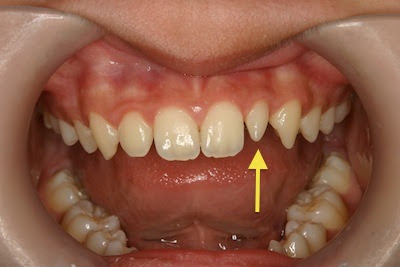

左上2番(矢印の向かって右側の歯)が生まれつき小ぶりの歯(矮小歯)に

なっています

このままでは見た目が悪いためダイレクトボンディングで治療する事にしました

反対側の歯は正常な形です

綺麗に自然に仕上がりました

これで笑うときに口元を手で隠さずに済みます